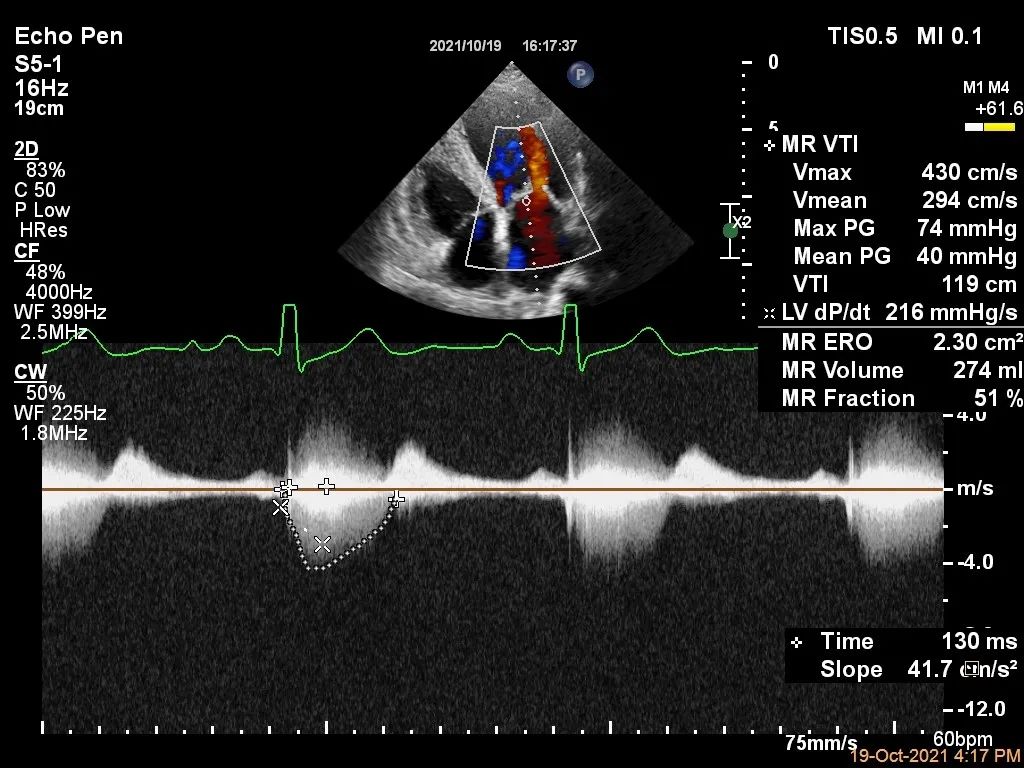

Bicom:MR(重度),反流束宽22mm,反流面积24.2cm²,PISA法定量EROA:2.3cm²,Rvol:274ml,RF:57%,r:16mm。

二尖瓣反流频谱呈全收缩期

肺静脉血流频谱呈收缩期反向